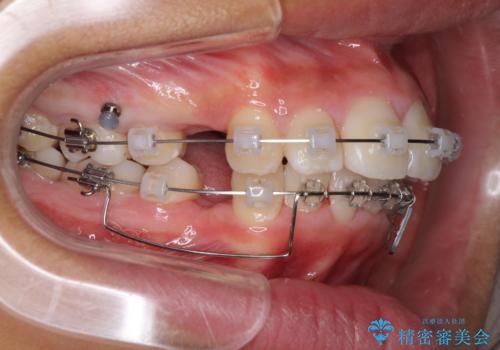

- クリアブラケット

- 治療期間

- 3年

口元を積極的に引っ込めるために、上下左右の第一小臼歯を4本抜歯することとしました。